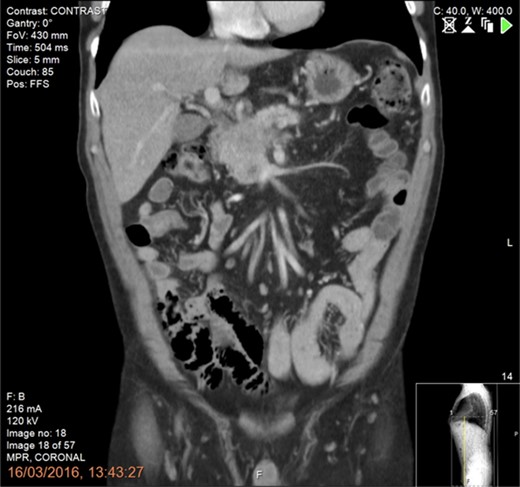

The patient underwent laparotomy, thorough exploration to rule out occult metastases followed by assessment of the tumour and its relation to the SMV/PV confluence and SMA using intraoperative ultrasound. Following kocherization, intraoperative IRE was performed with the guidance and presence of a consultant hepatopancreatobiliary interventional radiologist. We used two probes placed exactly 2 cm apart, at the level of the pancreatic neck under continuous ultrasound guidance. Placement of the needles should be atraumatic, avoiding injuries of underlying vital structures (PV, SMV, SMA). Since the purpose of the IRE was augmentation/accentuation of the resection margins and not in situ IRE of the tumour, we used only one pair of probes.

The probes were initially placed using the anterior and caudal to cephalad approaches along the SMV axis and between the SMV and SMA [6] (Fig. 3a and b). We used a 1.5 cm probe exposure to avoid high current conditions and potential thermal damage. Sequential pullbacks were performed in order to obtain adequate margins both superiorly and inferiorly. Standard default voltage of 1 500 V/cm is initiated with planned delivery of 90 pulses and a pulse width of 70–90 us. The current amperage draw was between 30 and 40 amps, which indicates a safe and effective electroporation. A posterior transduodenal approach was also used in order to accentuate posterior margin (Fig. 3c).

Intraoperative irreversible electroporation (IRE) margin accentuation using one pair of probes. The technique included probe placement using three different approaches including the anteroposterior (a), the caudo-cephalad between the superior mesenteric artery (SMA) and vein (SMV) (b) and the transduodenal (c) in order to augment the pancreatic, the SMV/ SMA groove and the posterior margins.